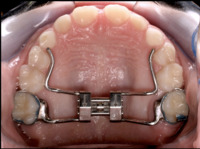

Upper and lower jaw functional expanders

A typical treatment for incorrectly positioned teeth (malocclusion) takes about 1 to 3 years to complete, with braces being altered slightly every 4 to 10 weeks by the specialists called orthodontists.[7] Orthodontists are dental specialists who are University-trained in the prevention, diagnosis and treatment of dental and facial irregularities. They provide a wide range of treatment options to straighten crooked teeth, fix bad bites and align the jaws correctly.[8] Multiple methods exist for adjusting malocclusion. In growing patients there are more options for treating skeletal discrepancies, either promoting or restricting growth using functional appliances, orthodontic headgear or a reverse pull facemask. Most orthodontic work is started during the early permanent dentition stage before skeletal growth is completed. If skeletal growth has completed, jaw surgery can be an option. Sometimes teeth are extracted to aid the orthodontic treatment (teeth are extracted in about half of all the cases, most commonly the premolars).[9]

Palatal expansion

Palatal expansion can be achieved using either fixed or removable appliances.[16]